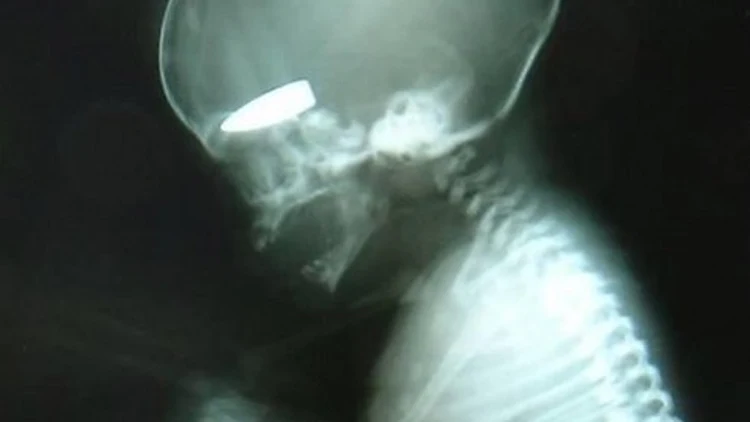

עובר שנטען כי נורה על ידי צלפים בסוריה | צילום: ללא קרדיט